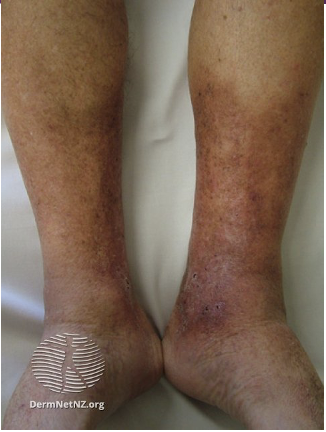

Quelle est la condition responsable de cette présentation clinique

e) insuffisance veineuse

e)